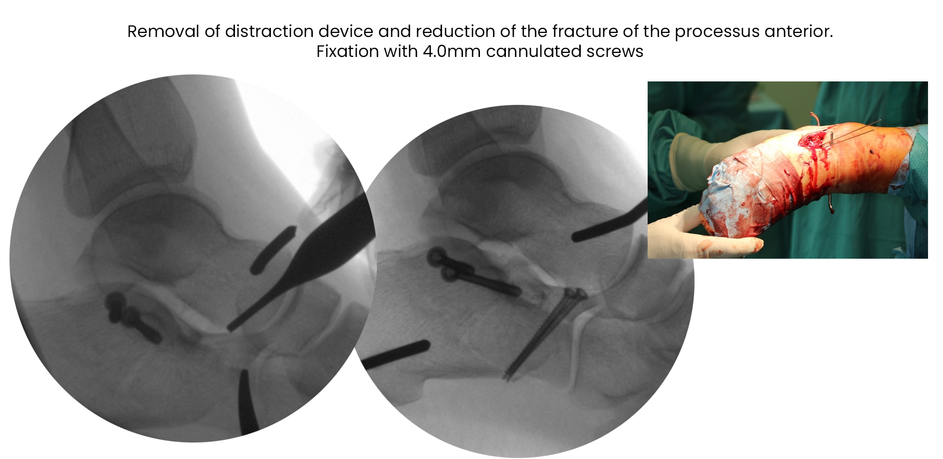

case 18ZJ, 23 years old, female, fall from horse, "atypical fracture" surgery after 2 days